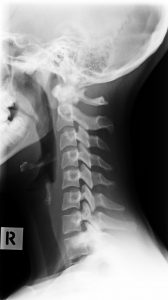

Phase One

Phase One Subluxation Degeneration

Phase One typically represents subluxations present for up to 20 years. In this early stage, the normal curve of the neck begins to change or flatten, and in some cases may even reverse completely. Disc spaces may start to show subtle changes, although the vertebral bodies still maintain clear borders.

Segmental motion may be affected, but general movement is often still relatively normal. More than 80% of people in Phase One experience no pain, meaning it can progress silently. If left untreated, Phase One will continue advancing.

Chiropractic reconstructive care for Phase One usually ranges from 6 to 18 months.